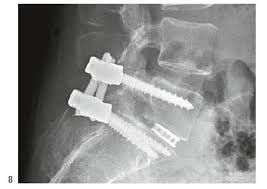

Spondylodese Op Wirbelsaulenversteifung Joimax